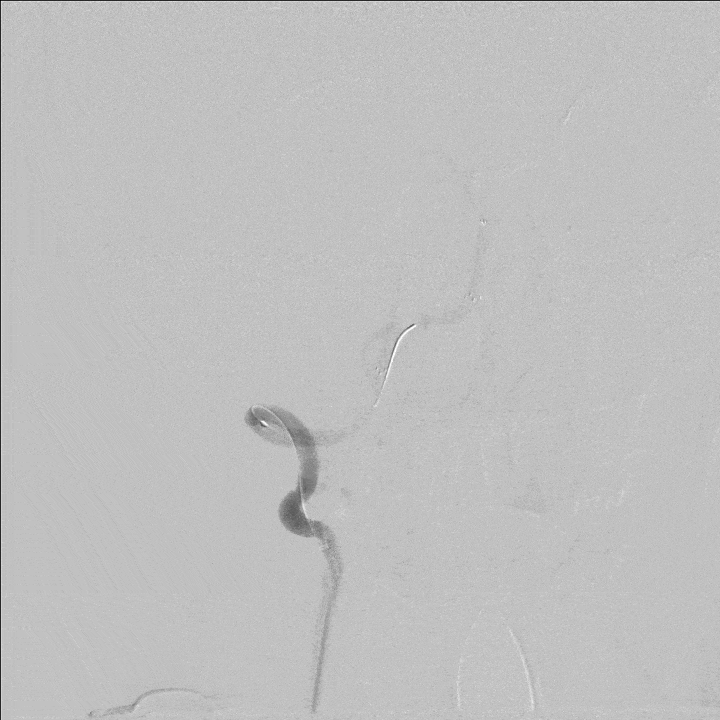

300cm微导丝携Gateway球囊到位,行球囊扩张及预扩张后造影。

1、本例患者反复出现神经功能障碍,血管评估提示双侧椎动脉V4段均为重度狭窄,左侧狭窄位置位于发出小脑后下动脉下方,紧邻小脑后下动脉,同时左侧小脑后下动脉起始段存在有重度狭窄,相对粗大。

2、右侧椎动脉V4段血管狭窄附近未见有明确血管分支,因此手术选择了行右侧椎动脉V4段球囊扩张及支架置入术,因双侧椎动脉V4段狭窄以远椎动脉及基底动脉汇合处血管良好,因此右侧椎动脉V4段狭窄处支架置入术后病人右侧椎动脉及远端基底动脉血流明显改善外,同时也可见到左侧椎动脉V4段逆向显影至左侧小脑后下动脉。同时避免了左侧椎动脉支架置入术中对左侧小脑后下动脉的影响导致小脑后下动脉缺血事件发生的可能。

3、Gateway球囊为半顺应性球囊,推送性能良好,术中缓慢扩张,可减少球囊移位、血管变形及夹层等,为后续支架置入提供了良好的条件。

4、EZ支架通过性好,释放顺畅,径向支撑力强,支架贴壁良好。